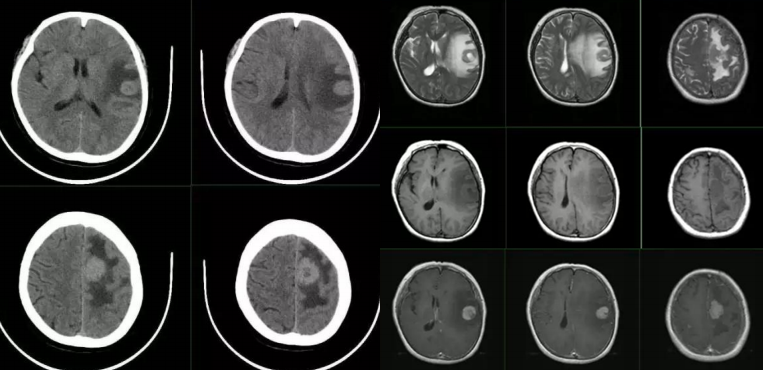

病例14

看图识病

答案:弥漫大B型细胞淋巴瘤。该病初发症状多为局限性表现,如肢体麻木、偏瘫、失语、共济失调等。 颅脑内压增高也很常见。肿瘤侵及胼胝体可见出现精神症状,侵及丘脑可出现觉醒障碍。好发部位为额顶叶深部、基底节、脑室周围和胼胝体、下丘脑、小脑也可累及,常浸润室管膜下组织,通过脑脊液向脑脊膜扩散。国内有的学者认为“握拳样”或“脑回样”强化,仅在淋巴瘤病例中看到。